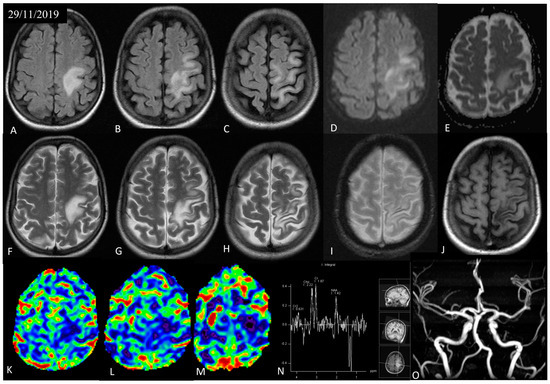

3.1. Case Presentation